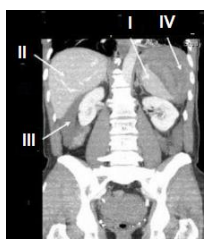

Observe a imagem radiológica abaixo:

Fonte: https://www.lecturio.com/pt/concepts/imagem-do-baco/

Os números I, II, III e IV refere-se a quais órgãos?